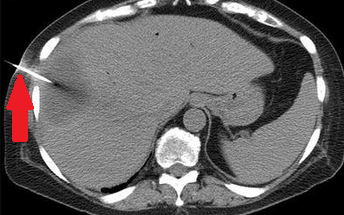

Polycystic liver disease. Red arrow. Infected hepatic cyst (Courtesy Dr. V. Penopoulos)